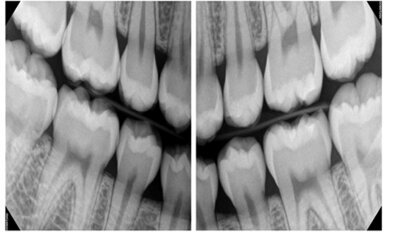

Digital imaging firm’s reputation for reliability is 50 years in the making

MILWAUKEE, Wis.: The biggest challenge Instrumentarium Dental faces when encouraging existing clients to upgrade equipment is convincing them to let go of ...

save